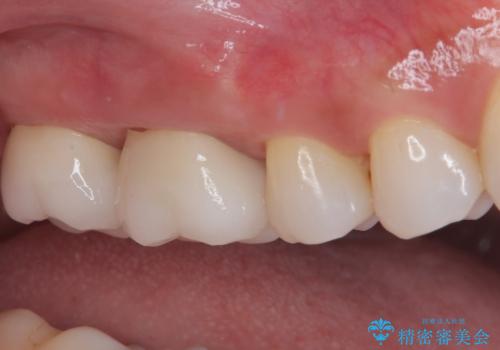

隣接する部分の間のむし歯が歯肉の奥深くにまで及んでおり、歯肉が腫れやすい状態となっていたため、歯肉の切除並びに歯槽骨の形態修正を行い、虫歯が歯肉の外に出てくるようにした上で、オールセラミックにて補綴することとしました。

歯間ブラシを通す度に出血をするのは、ご自身の磨き方が悪いからと思っていらっしゃいましたが、治療後は全く出血することがなくなり、患者様には大変満足していただきました。